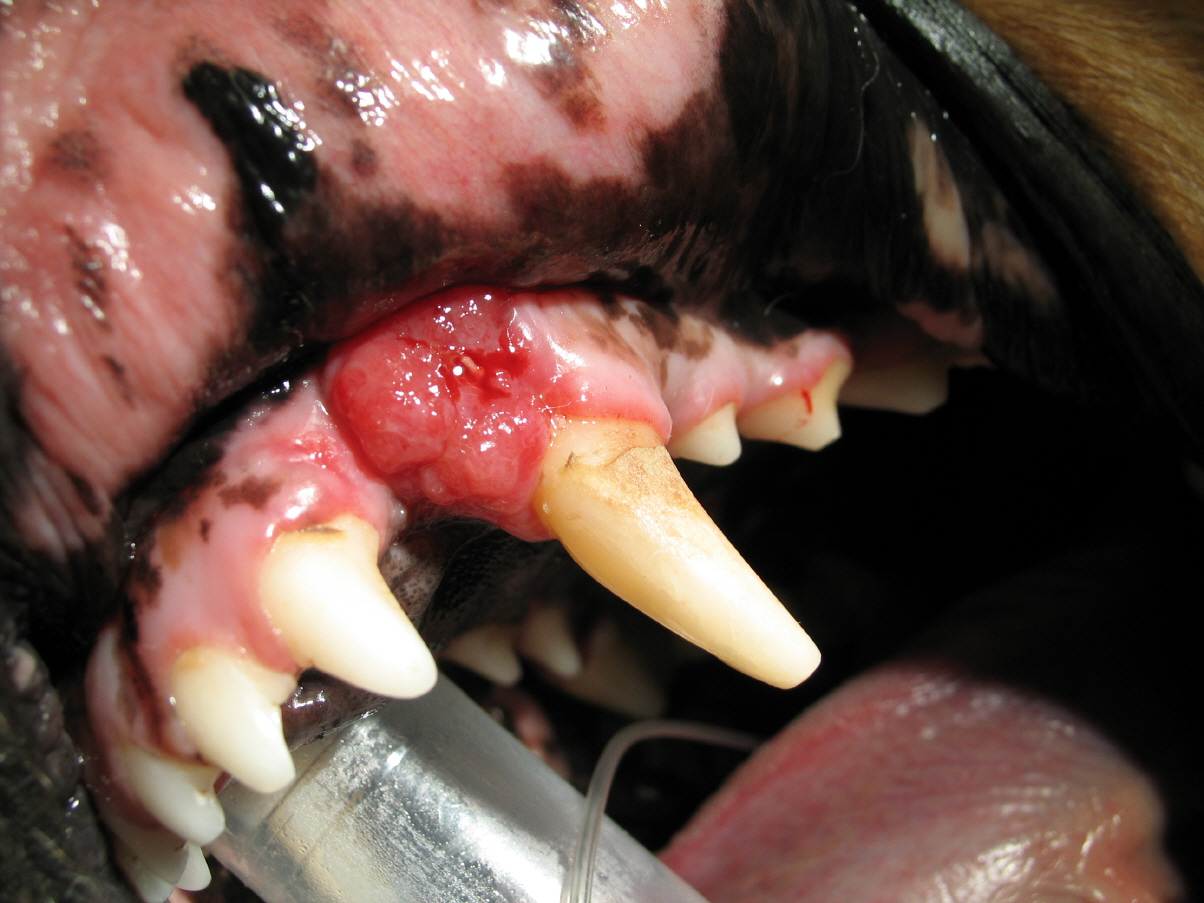

Max ist ein 10 Jahre alter Golden Retriever, der bei uns in der Praxis 2005 wegen eines Geschwüres im Oberkiefer vorgestellt wurde.

Zuerst wurde eine Probe entnommen und zur weiteren Untersuchung an einen Pathologen zur Auswertung gesendet.

Das Ergebnis war leider erschreckend, da es sich um einen bösartigen Tumor handelte, welcher so schnell wie möglich entfernt werden musste. Max bekam einen Termin zur Operation.

Operation

Aufgrund des Einwachsens des Tumores in den Knochen musste bei Max ein Teil des Oberkiefers und 3 Zähne entfernt werden. Max konnte noch am selben Tag entlassen werden. Er erhielt über einige Tage ein Schmerzmittel. Bereits am Tag nach der Operation hatte Max schon wieder einen guten Appetit.